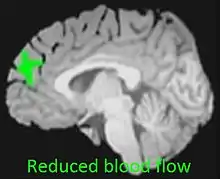

| Reduced blood flow in prefrontal cortex of adolescent cannabis users[1] | |

The endocannabinoid system is directly involved in adolescent brain development.[22] Adolescent cannabis users are therefore particularly vulnerable to the potential adverse effects of cannabis use.[22] Adolescent cannabis use is associated with increased cannabis misuse as an adult, issues with memory and concentration, long-term cognitive complications, and poor psychiatric outcomes including social anxiety, suicidality and addiction.[23][24][25]